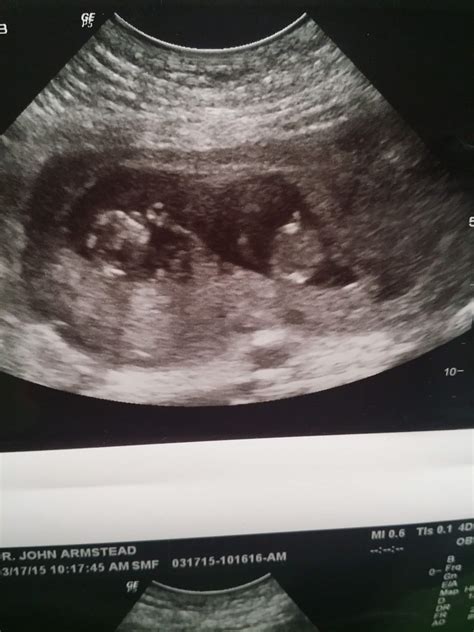

An 11 weeks pregnant ultrasound is typically performed as part of routine prenatal care. This ultrasound is often referred to as the "nuchal translucency" scan. It is usually conducted between 10 weeks and 13 weeks and 6 days of pregnancy. The primary goal of this ultrasound is to assess the baby's development and screen for certain chromosomal abnormalities, such as Down syndrome.

• Visualization of the Baby: At 11 weeks, your baby is about the size of a fig, measuring approximately 1.6 inches (4.1 centimeters) in length and weighing around 0.25 ounces (7 grams). The ultrasound will show the baby's head, body, and limbs, although the details will be more pronounced in later ultrasounds.

• Nuchal Translucency Measurement: This measurement assesses the fluid-filled space at the back of the baby's neck. Increased fluid in this area can indicate a higher risk of chromosomal abnormalities.

• Other Structures: The ultrasound may also visualize the baby's spine, stomach, and other internal structures, providing a comprehensive view of your baby's development.